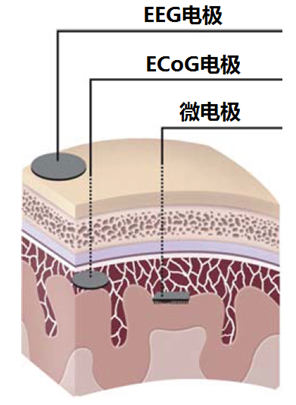

本书译自Jonathan R.Wolpaw(美)和Elizabeth Winter Wolpaw(美)编著的经典著作《Brain–Computer Interfaces: Principles and Practice》,是一部关于BCI原理、方法和实践的专著,全面、系统、深入、具体地介绍了BCI的基础、实现方法和应用。书中着重指出了BCI最重要的问题、信号采集问题、验证和宣传问题、可靠性问题;提出了BCI六个重要的主题;详细论述了BCI的设计、实施和操作,包括从大脑内和从大脑外采集脑信号、BCI信号处理、特征提取和转化、BCI硬件和软件、BCI操作协议及BCI应用。此外,本书特别注重原理与实际应用的紧密结合,在上述共性原理和方法的基础上,深入研究了现有的7种BCI的具体原理和实现方法,分别是基于P300事件相关电位、基于感觉运动节律、基于稳态视觉诱发电位/慢变皮层电位、基于皮层脑电活动、利用运动皮层记录的信号、利用在顶区或运动前期皮层记录的信号、基于大脑代谢信号的BCI,这些具体实例便于读者更加深刻地理解和运用原理及方法。